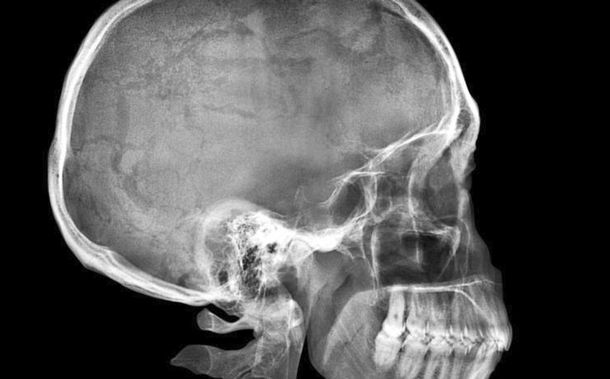

Médicos del Atlanta Medical Center, en Estados Unidos, se sorprendieron al hallar una bala en la parte trasera del cráneo de una mujer que concurrió para una consulta por dolores de cabeza.

La paciente, de 41 años, no recordaba haber sido baleada, informó el FBI.